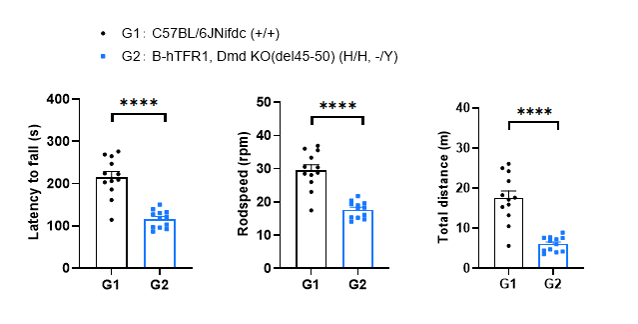

Behavioral performance in wild-type C57BL/6JNifdc and homozygous B-hTFR1, Dmd KO(del45-50) mice. Rotarod tests were conducted to assay the behavioral performance in wild-type C57BL/6JNifdc and homozygous B-hTFR1, Dmd KO(del45-50) mice (male, 3-month-old, n=12). Rotarod tests were performed to assay the motor coordination. The latency to fall, rodspeed and total distance were significantly decreased in homozygous B-hTFR1, Dmd KO(del45-50) mice, showing the impairment of motor coordination and balance. Values are expressed as mean ± SEM. Significance was determined by unpaired t test. *P < 0.05, **P < 0.01, ***P < 0.001, ****P < 0.0001.